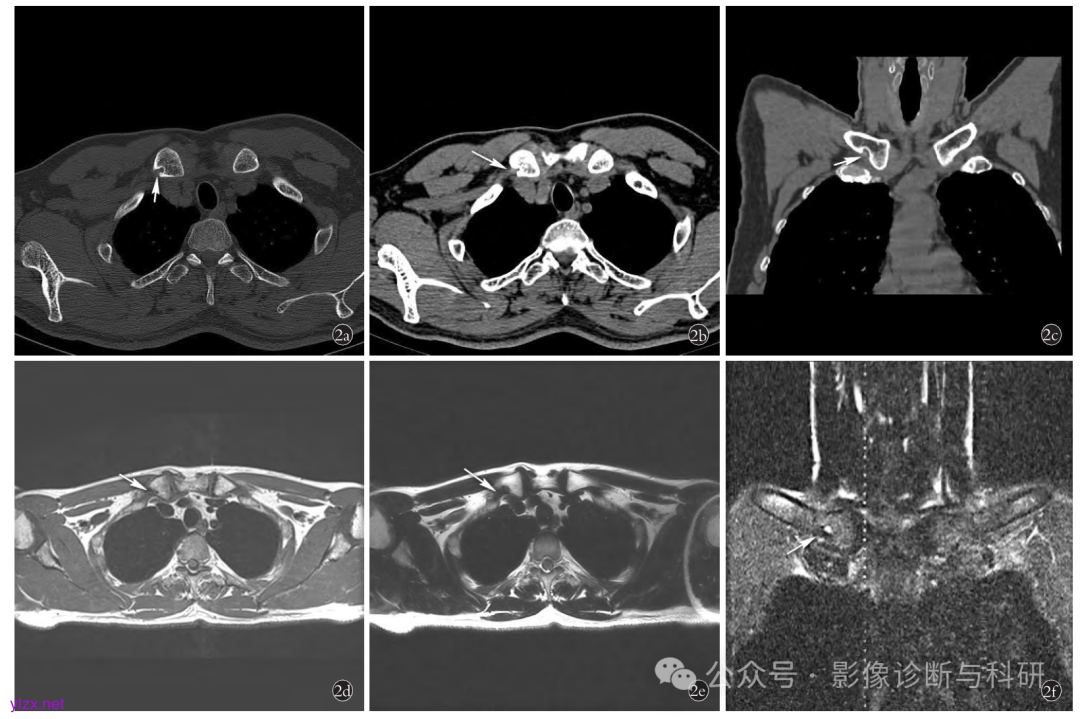

患者,男, 48 岁,锁骨棱形窝 2a , 2b , 2c. 右侧锁骨内侧端可见小圆形骨质缺损,边缘硬化,内侧端形态呈鱼钩样(箭头所示);横断位及冠状位软组织窗可见小条状软组织灶伸入(箭头所示) 2d , 2e , 2f. 分别为 T1WI 、 T2WI 、 T2WI 压脂图像:右侧锁骨内侧端可见小圆形骨质缺损,长T1 短 T2 信号, T2 压脂可见低信号边缘可见小点状高信号灶(来源于中国骨伤杂志)